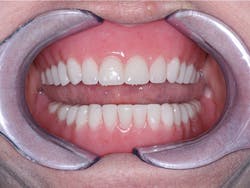

Another big reason most edentulous patients have not had implants is the constant promotion by newspapers, magazines, and TV of complex, extensive, and expensive techniques provided by some dentists and implant manufacturers. Yes, I agree that these complex plans are acceptable for some patients, but I'm convinced they're well beyond the budgets of most Americans. Thousands of edentulous patients have not been introduced to less expensive and less invasive implant treatment procedures. The majority of dentists are not using implants for edentulous patients. This treatment need is enormous, and it's only waiting for dentists to educate patients and make dentures more successful (Figures 1-3).

Figure 1 - Initial healing on two conventional diameter root form implants planned to help support and retain a mandibular complete denture.